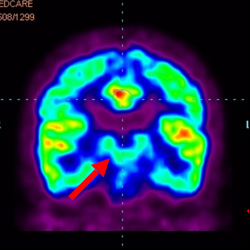

細(xì)胞治療前 PET CT 掃描顯示神經(jīng)組織中的藍(lán)/黑色區(qū)域,表明腦癱引起的大腦損傷。

腦癱細(xì)胞療法, 腦癱治療